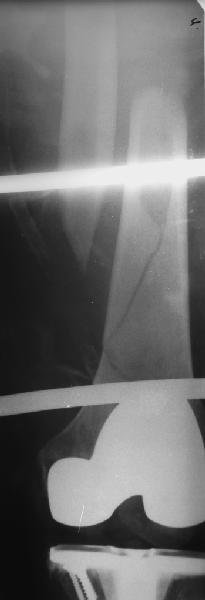

В приложении - недавний перипротезный перелом.